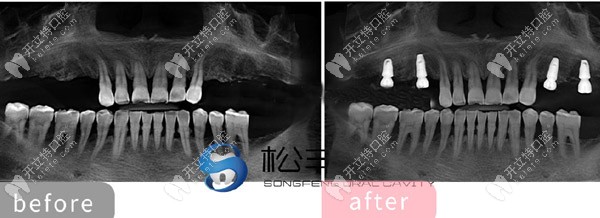

★ 顧客下頜多顆缺失,

上海松豐齒科的蔣院長(zhǎng)采用了即刻種植技術(shù),讓顧客當(dāng)天就了下半口牙。

下頜即刻種植

★ 多顆牙齒缺失種植展示

多顆牙齒缺失種植展示